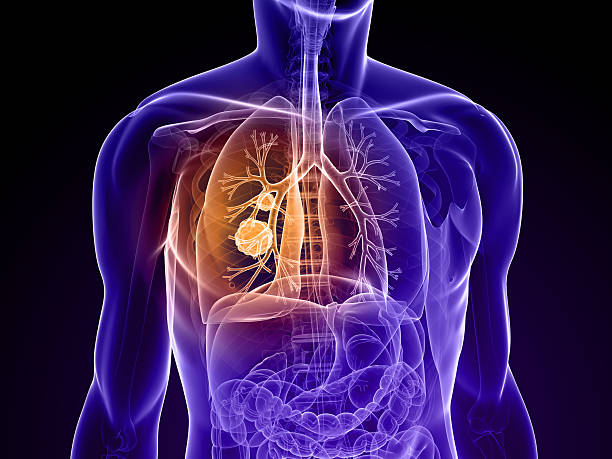

폐암은 초기에는 증상이 미미하거나 없을 수 있습니다. 그러나 조기에 발견하고 진단받으면 치료의 성공률이 훨씬 높아집니다. 초기에 폐암을 발견하면 조기 치료를 시작하여 종양의 성장과 전이를 제한할 수 있습니다. 뿐만 아니라, 치료에 있어 다양한 치료 방법을 활용할 수 있어 폐암 초기 증상을 잘 알고 있는 것이 중요합니다.